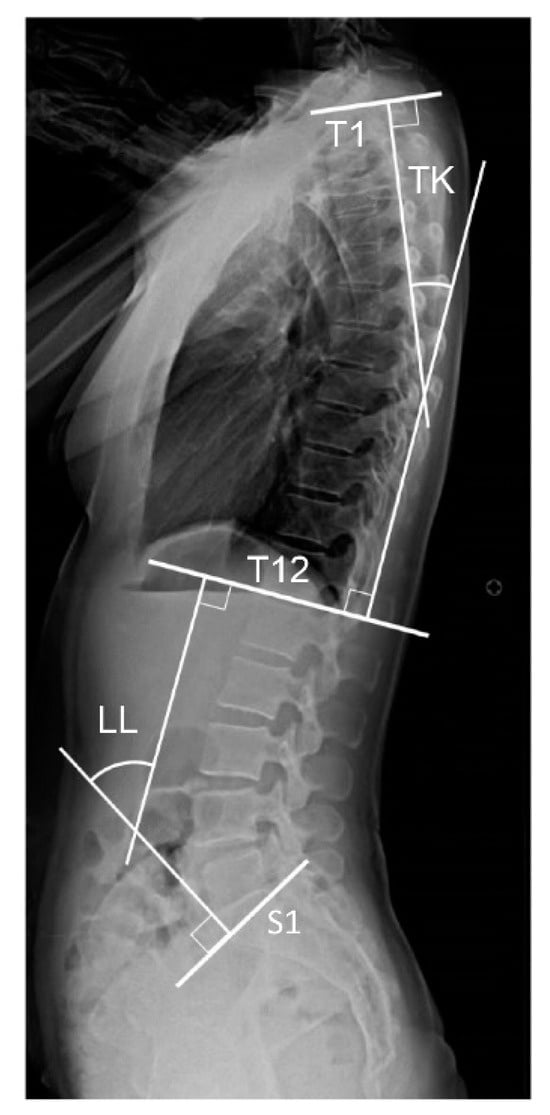

2.2. Measurement of Pelvic and Spinal Parameters

| TK | 35.1 ± 12.0 | 39.6 ± 8.4 | 35.9 ± 8.6 | 33.5 ± 8.6 | 32.1 ± 9.8 |

| LL | 48.5 ± 12.1 | 53.8 ± 10.8 | 50.3 ± 11.6 | 47.6 ± 11.9 | 43.5 ± 14.0 |